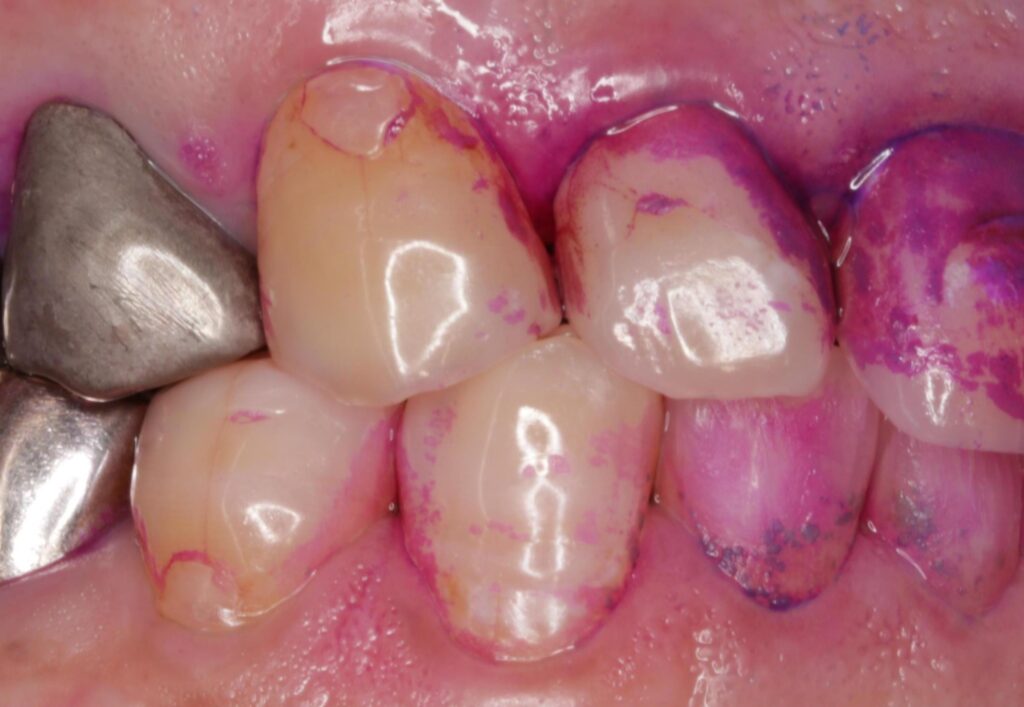

歯と歯の間の汚れ

歯ブラシの毛先が届くのは、お口全体の約6割と言われています。残りの4割、つまり歯間にある汚れが発酵し、ニオイを放つのです。フロスや歯間ブラシを使っていない方は、ここが原因になっていることがほとんどです。

👉️実際には、歯周病と歯と歯の間の汚れが重なっているケースが多く見られます。